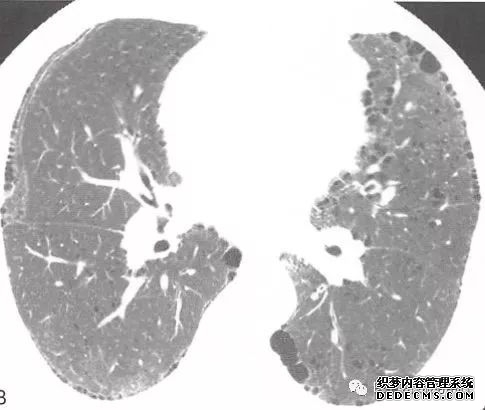

肺转移瘤的十种不典型CT表现